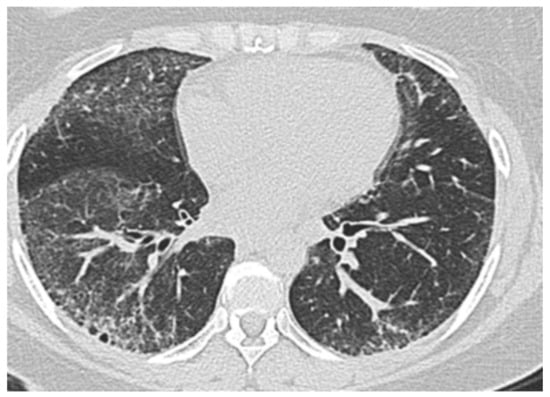

3.2. Interstitial Lung Disease-Associated PH in SSc

- Ryu, J.H.; Krowka, M.J.; Pellikka, P.A.; Swanson, K.L.; McGoon, M.D. Pulmonary hypertension in patients with interstitial lung diseases. Mayo Clin. Proc. 2007, 82, 342–350. [Google Scholar] [CrossRef]

- Hurdman, J.; Condliffe, R.; Elliot, C.; Davies, C.; Hill, C.; Wild, J.; Capener, D.; Sephton, P.; Hamilton, N.; Armstrong, I.; et al. ASPIRE registry: Assessing the Spectrum of Pulmonary hypertension Identified at a REferral centre. Eur. Respir. J. 2011, 39, 945–955. [Google Scholar] [CrossRef] [PubMed]

- Le Pavec, J.; Girgis, R.E.; Lechtzin, N.; Mathai, S.C.; Launay, D.; Hummers, L.K.; Zaiman, A.; Sitbon, O.; Simonneau, G.; Humbert, M.; et al. Systemic sclerosis-related pulmonary hypertension associated with interstitial lung disease: Impact of pulmonary arterial hypertension therapies. Arthritis Rheum. 2011, 63, 2456–2464. [Google Scholar] [CrossRef]

- Mathai, S.C.; Hummers, L.K.; Champion, H.C.; Wigley, F.M.; Zaiman, A.; Hassoun, P.M.; Girgis, R.E. Survival in pulmonary hypertension associated with the scleroderma spectrum of diseases: Impact of interstitial lung disease. Arthritis Rheum. 2009, 60, 569–577. [Google Scholar] [CrossRef] [PubMed]